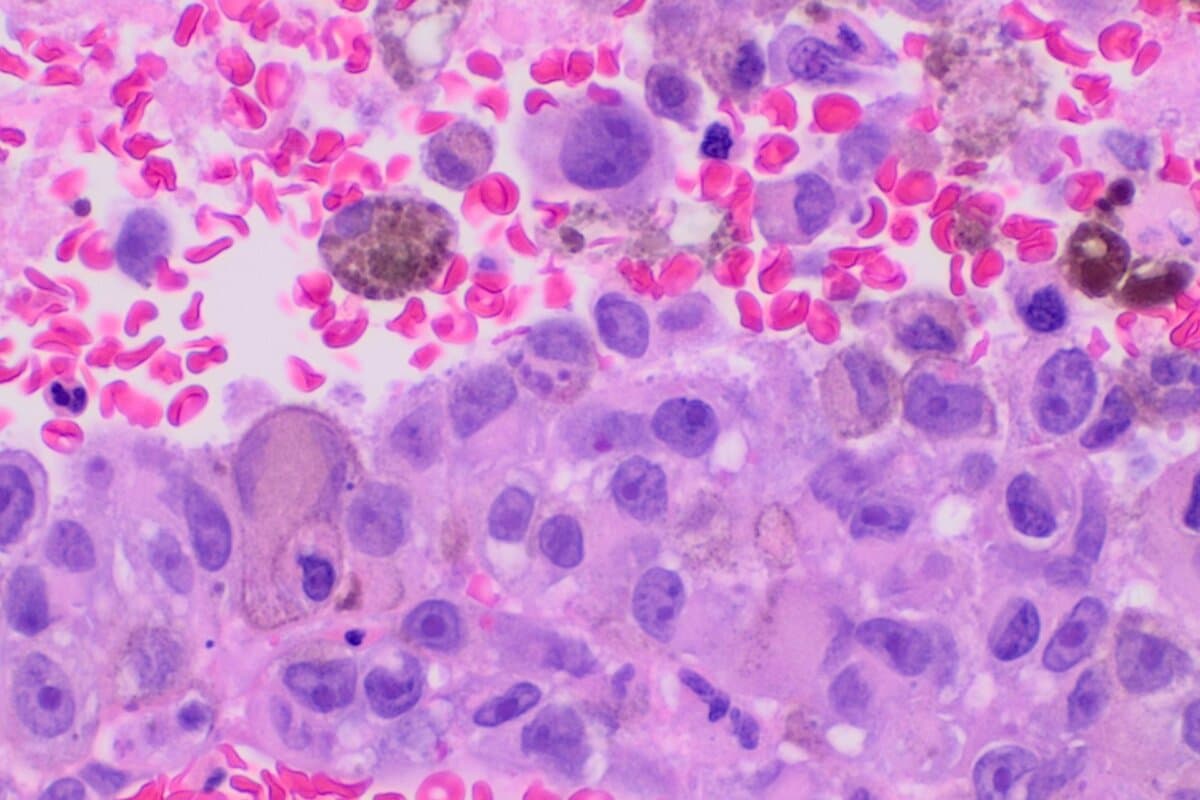

Weder das orale noch das topische IMQ allein beeinflusste die Tumorprogression. Der kombinierte Ansatz hingegen bewirkte eine signifikante Verringerung des Tumorwachstums, eine verstärkte Tumornekrose und eine reduzierte Blutgefäßbildung. Die Kombinationsbehandlung war selbst bei größeren Tumoren wirksam. Sie zeigte somit Potenzial zur Verringerung von Metastasen, was auf eine systemische Immunreaktion hindeutet.